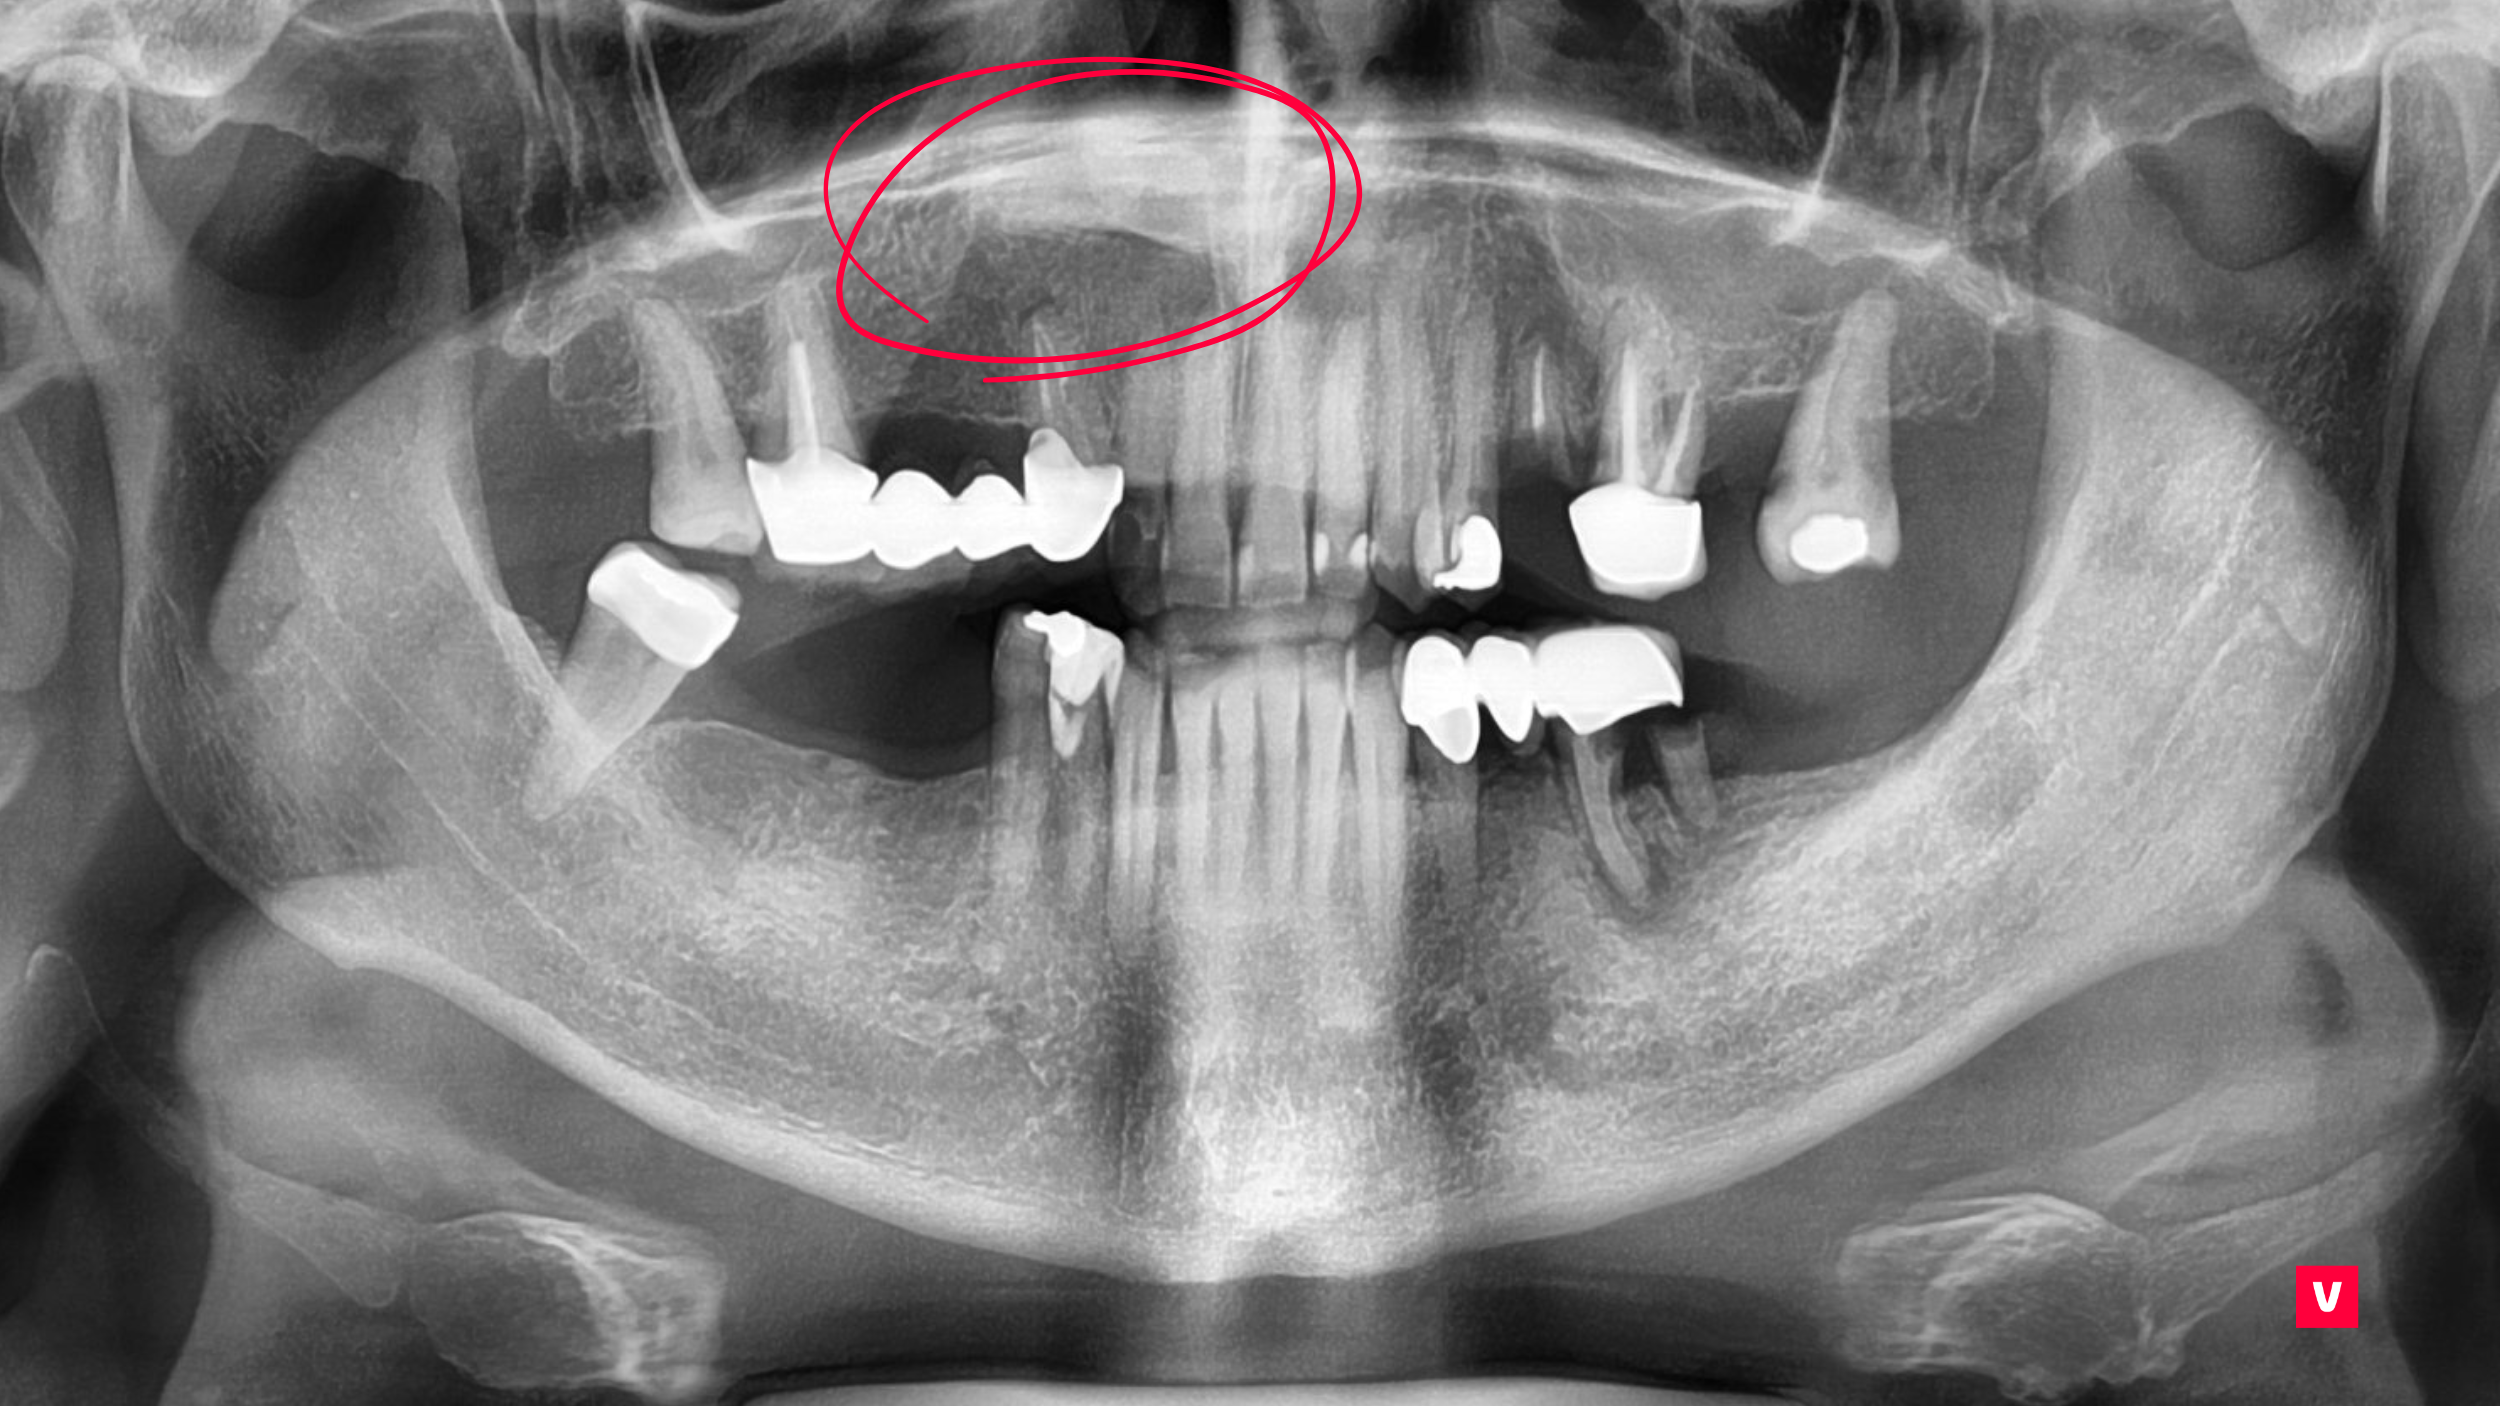

În studiul de caz pe care îl dezbatem în acest articol vom vedea cum depistarea unei astfel de complicații s-a putut observa doar în cazul unei examinări detaliate, ceea ce nu s-a putut observa după o scanare OPG (ortopantomografie), din cauza asimetriei din regiunea maxilarului. Doar cu ajutorul unei imagini CBCT 3D s-a văzut că pacientul are un dinte ascuns în regiunea maxilarului superior drept care ar fi putut provoca complicații grave dacă nu ar fi fost descoperit la timp.

După cum se poate observa în acest studiu de caz prezentat, dintele ascuns în maxilar este mult mai aproape decât pare la o scanare OPG obișnuită. Acest lucru ar putea cauza unele probleme în timpul procedurilor stomatologice. Medicul stomatolog a identificat anomalia la timp, prevenind astfel complicațiile.